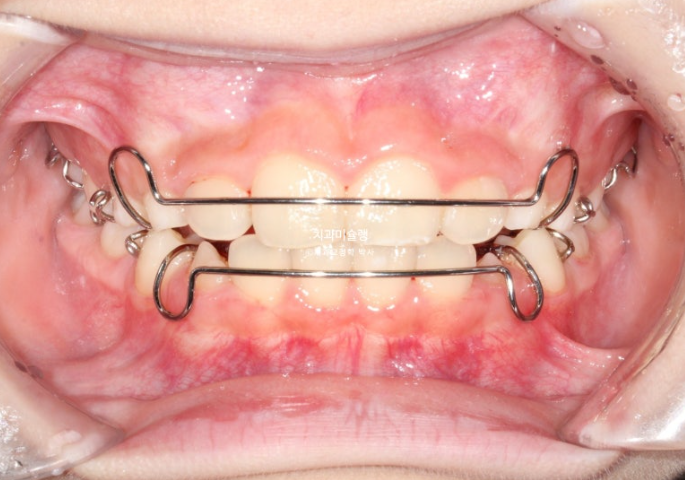

23년 10월, 교정치료를 위해 온 어린이 입니다.

앞니 두 개 높낮이 차이, 앞니가 깊게 물리는 과개교합이 보입니다.

앞니 네개 중 옆 앞니 즉 측절치가 나올 공간이 좁습니다.

아래도 마찬가지 입니다.

앞니가 벌써 삐뚤삐뚤 합니다.

송곳니가 나올때는 어떻게 될까요?

덧니 100% 예약입니다.

인비절라인 퍼스트 치료에 들어갔습니다.

첫세트 장치는 23개 입니다.